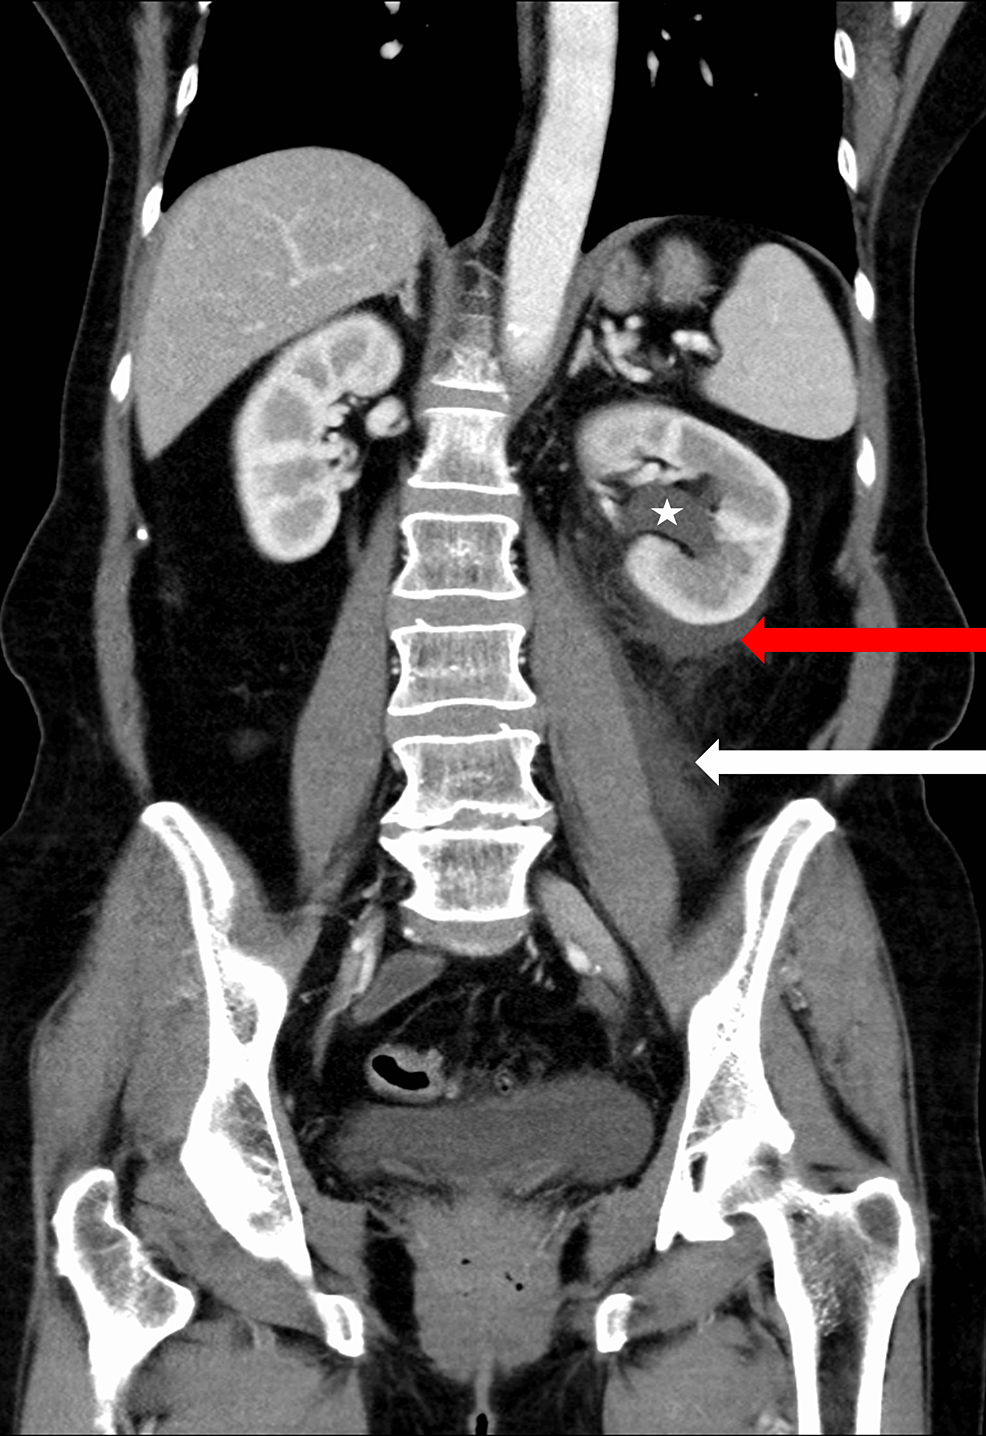

From www.semanticscholar.org

Ureteral Dissection Is a Risky Factor for Ureteral Rupture, the First Case Report. Semantic Can A Ureter Burst Blood clots in urine, or hematuria, can be caused by various factors, such as exercise, injury, medications, enlarged prostate, utis, stones, and cancer. Ureter obstruction is a condition that blocks the flow of urine from the kidney to the bladder, causing pain and kidney damage. Ureteral obstruction is a blockage in one or both of your ureters that prevents pee. Can A Ureter Burst.

From surgicalcasereports.springeropen.com

Spontaneous ureteral rupture caused by iliac aneurysm a case report Surgical Case Reports Can A Ureter Burst Urinary retention is when your bladder doesn’t empty when you pee. An unrecognized or mismanaged ureteral injury can lead to significant complications, including urinoma, abscess, ureteral stricture, and potential loss of ipsilateral kidney or. Blood clots in urine, or hematuria, can be caused by various factors, such as exercise, injury, medications, enlarged prostate, utis, stones, and cancer. Learn about the. Can A Ureter Burst.

Spontaneous ureteral rupture caused by iliac aneurysm a case report Surgical Case Reports Can A Ureter Burst An unrecognized or mismanaged ureteral injury can lead to significant complications, including urinoma, abscess, ureteral stricture, and potential loss of ipsilateral kidney or. It can be acute or chronic and can be caused by. Ureteral stents are temporary devices to prevent or treat urinary tract obstruction, but they can cause problems if left in place too long. Urinary retention is. Can A Ureter Burst.